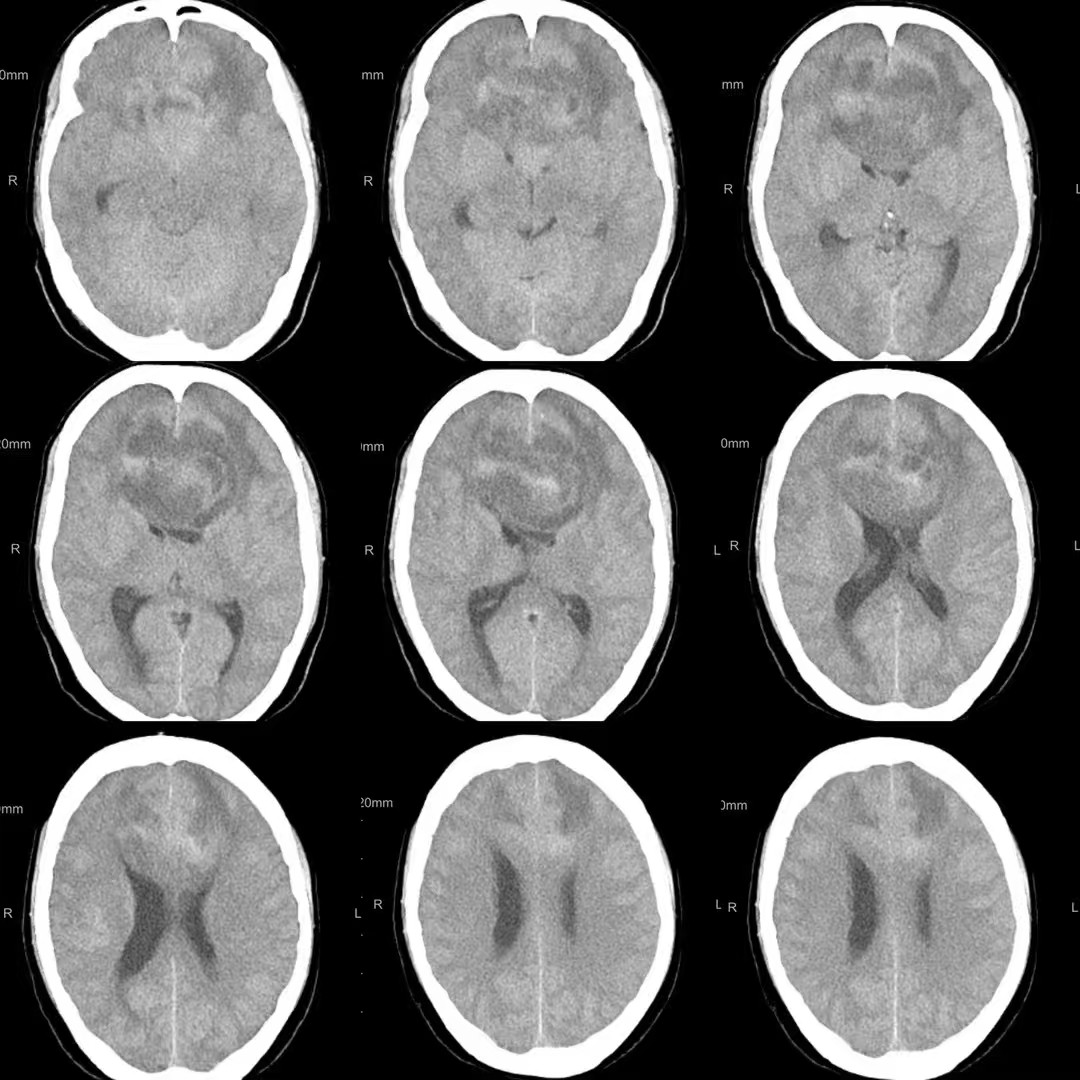

患者,女性,58岁,因“反应迟钝、记忆力下降1月,加重伴头痛、恶心、呕吐1周”入院。